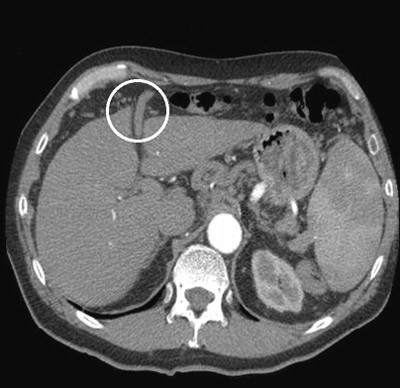

Tilsendte røntgenundersøkelser fra henvisende sykehus ble revurdert. Som bifunn på CT av thorax/ øvre abdomen tatt ti måneder før innleggelse på Rikshospitalet ble det bemerket at det forelå åpentstående umbilikalvene samt slyngede vener i øvre abdomen som ga mistanke om portal hypertensjon (fig 2).

Påvisning av åpentstående eller rekanalisert umbilikalvene på CT kan være et uspesifikt funn, men skyldes ofte portal hypertensjon med utvikling av kollateralt kretsløp. Portal hypertensjon kan være assosiert med hypoksemi via flere mekanismer: portopulmonal hypertensjon, hypoksemi sekundært til hydrothorax/ascites ved leversvikt eller hepatopulmonalt syndrom.

Det ble gjort CT av lever/øvre abdomen med intravenøs kontrast som viste at leveren var liten med grovbuklet overflate som ved cirrhose og at det forelå massivt utviklet kollateralkretsløp i form av rekanalisert vena umbilicalis samt kollateraler i milthilus og langs ventrikkelens minorside til distale oesophagus som tegn på portal hypertensjon. Det var ingen fokale lesjoner.